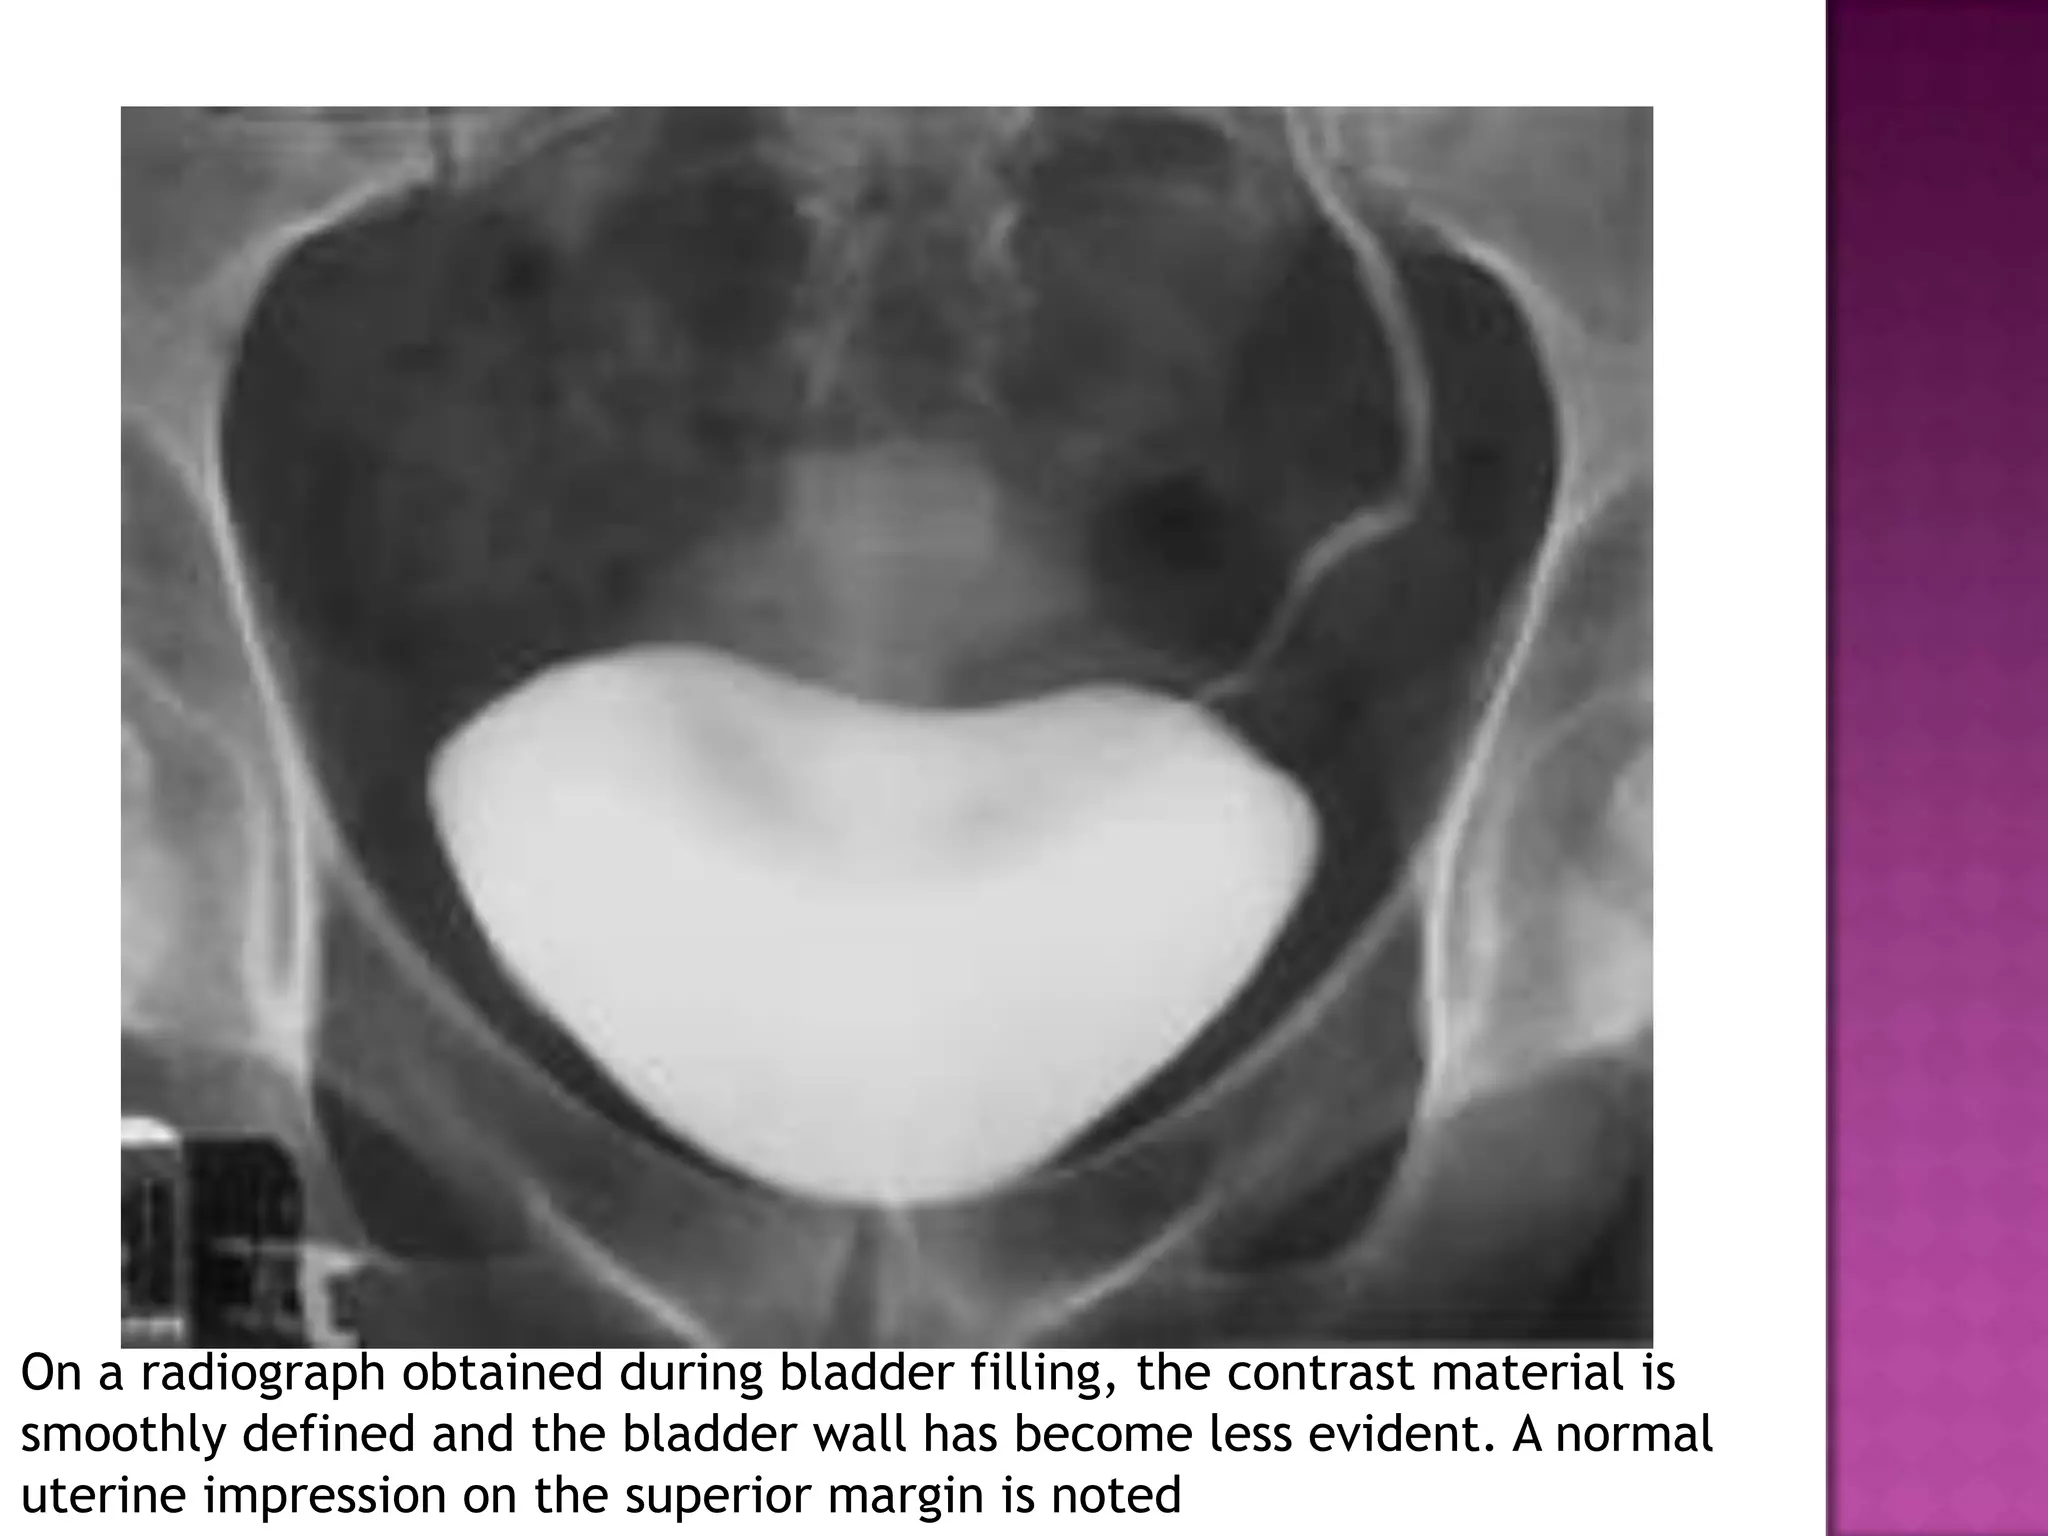

On a radiograph obtained during bladder filling, the contrast material is

smoothly defined and the bladder wall has become less evident. A normal

uterine impression on the superior margin is noted

On a radiographobtained during bladder filling, the contrast material is smoothly defined and the bladder wall has become less evident. A normal uterine impression on the superior margin is noted